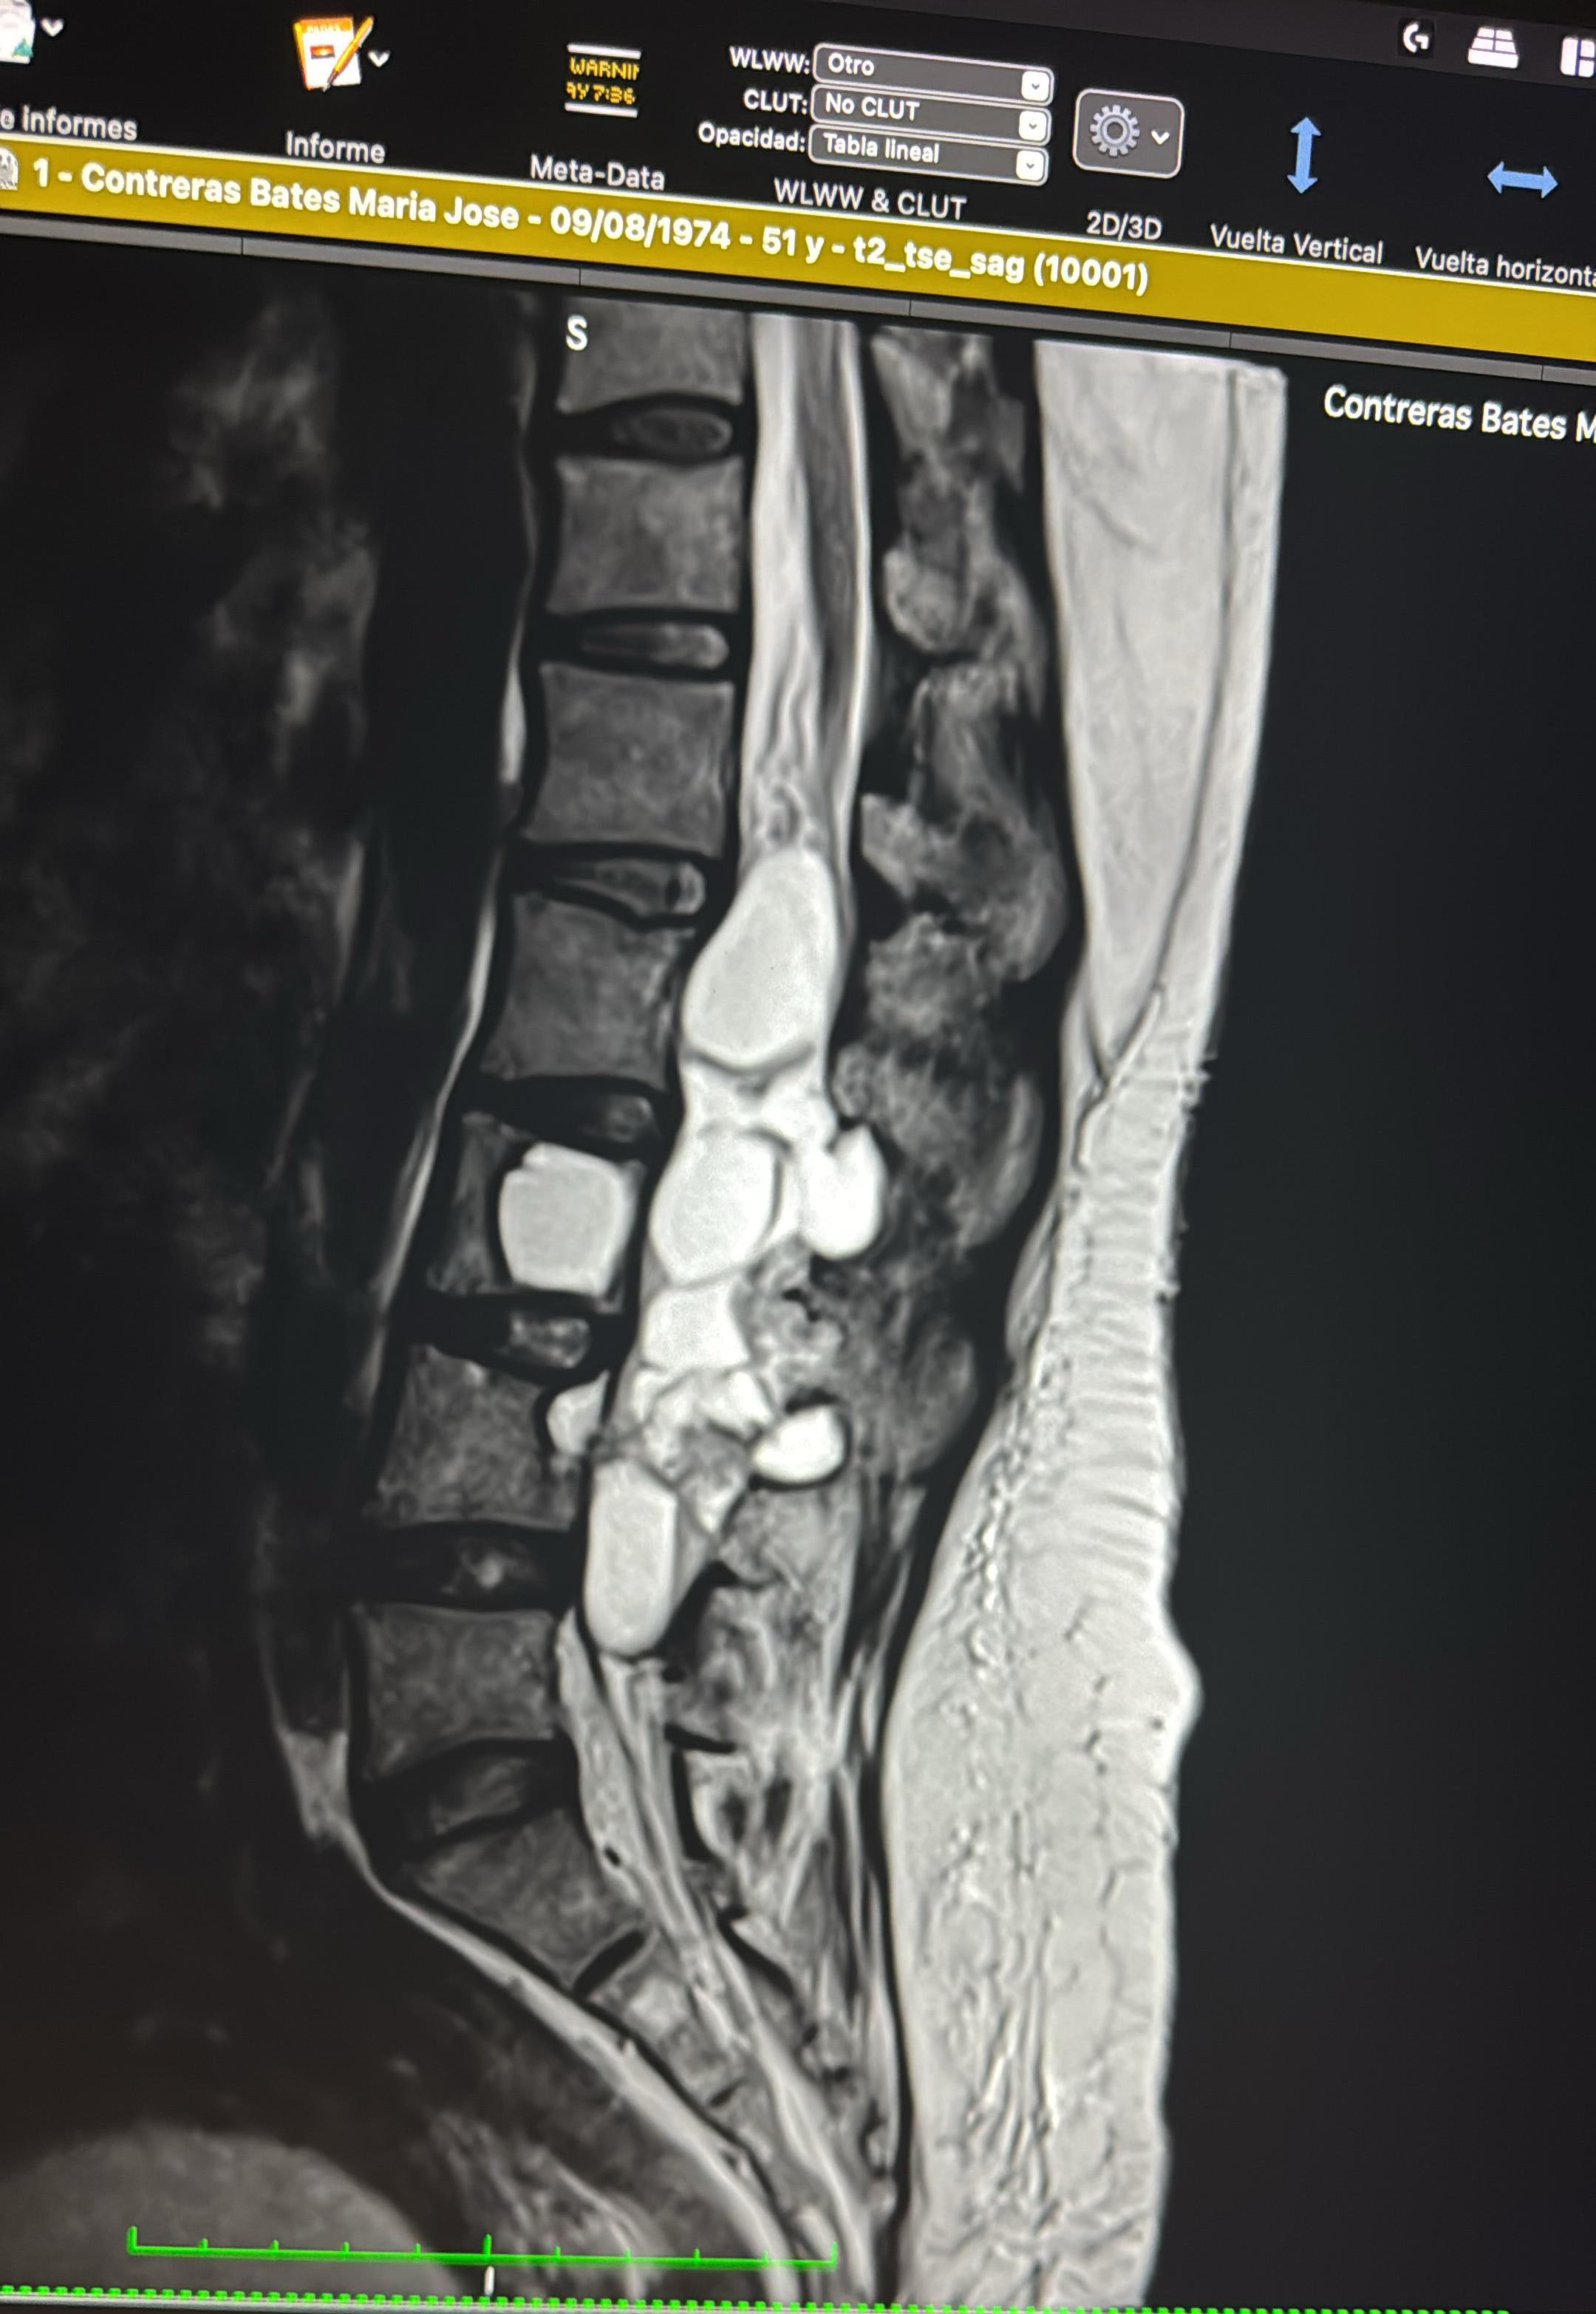

Hace algún tiempo comencé a notar que perdía fuerza en mi pie izquierdo y continuó en la parte pélvica y en mis piernas, lo que me ha ido limitando cada día más. Tras varios estudios, y luego de consultar con varios médicos, descubrieron que tengo quistes aracnoideos en la columna lumbar. Estos quistes han crecido mucho ya ahora presionan los nervios, causando dolor intenso, debilidad y dificultad para moverme con normalidad, 2 de esos quistes se incrustaron en mis vertebras.

He intentado diferentes tratamientos, pero lamentablemente la única solución definitiva es una cirugía de columna lumbar para retirar los quistes y liberar los nervios afectados antes que tengan daño irreversible.